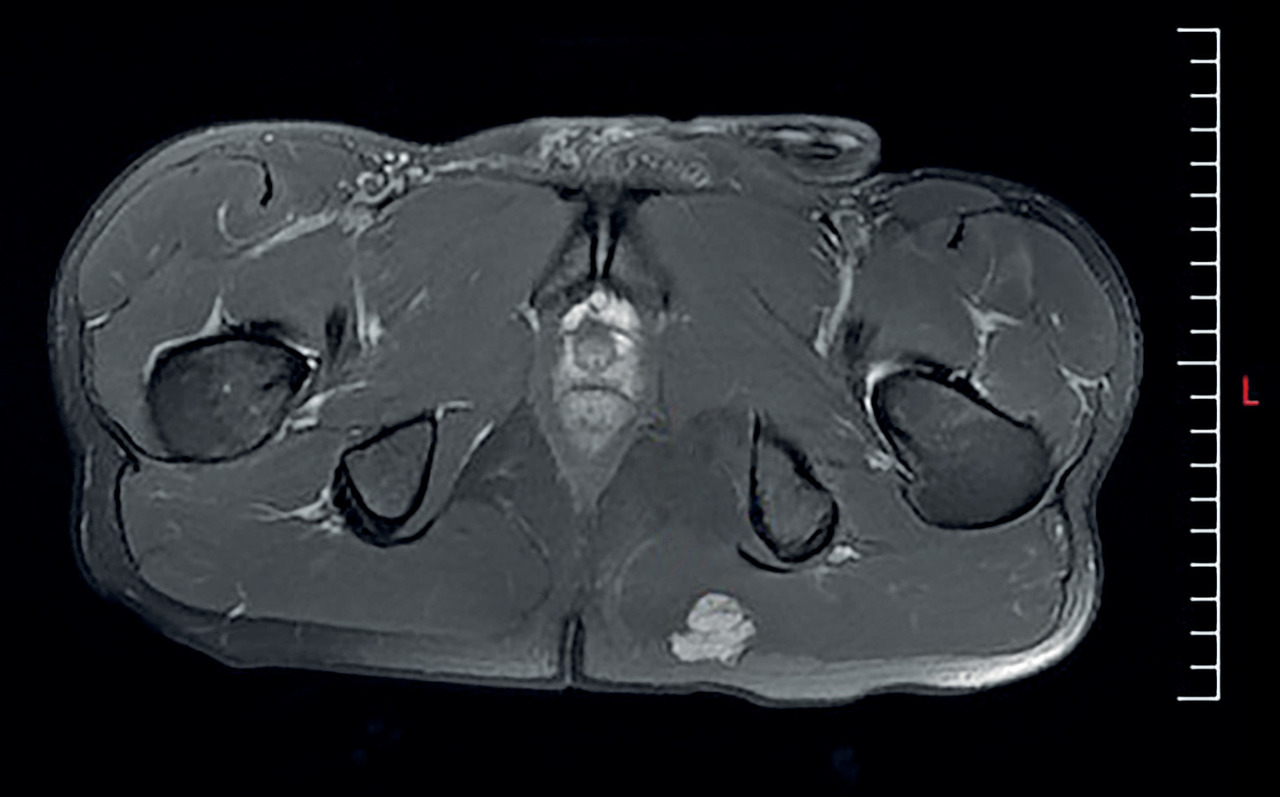

L’IRM fournit le diagnostic, rassurant (figure).

Développée dans le muscle grand glutéal (ex-grand fessier), la tumeur est limitée et superficielle, ce qui est en faveur de séquelles traumatiques et d’une MOC.

La radiographie est souvent normale et l’échographie peu spécifique ; la TDM montre une tuméfaction au sein des tissus mous. L’IRM révèle une masse dans le muscle et dans certains cas un niveau liquide-liquide. Cette image est rehaussée par l’injection de gadolinium.